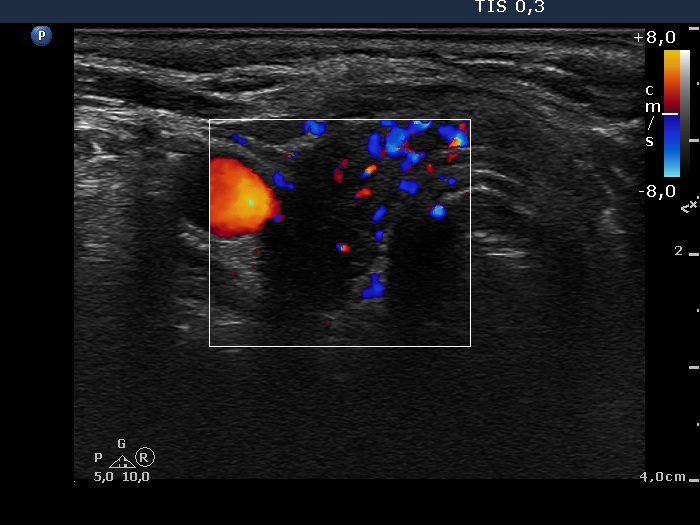

Ultrasonography: The thyroid was hypoechogenic. A distinct lesion was detected which was located lower to the lower pole of the right lobe.

Aspiration cytology benign lesion. Wash-out thyroglobulin level was 0 ng/mL while wash-out parathormone level was above 474 pg/mL.